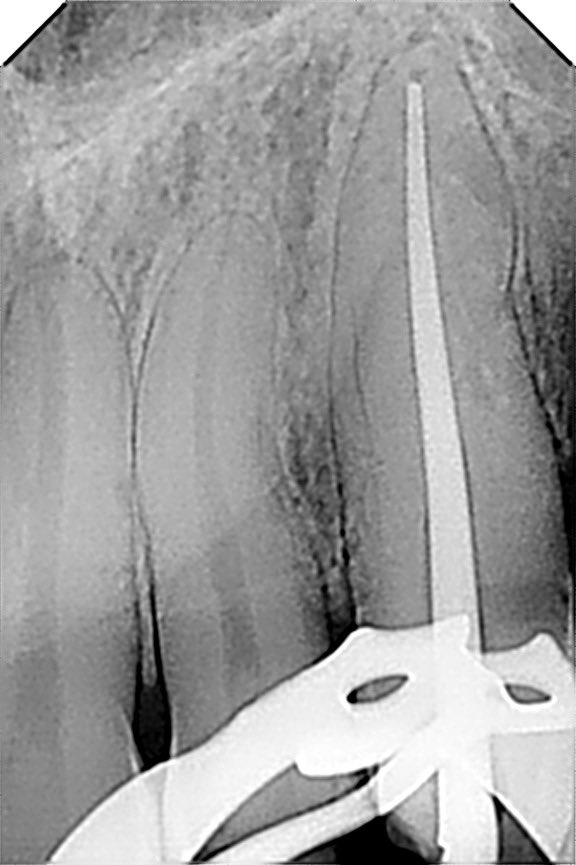

طبيب مقيم في علاج الجذور و عصب الأسنان 🦷 🦷 Endodontic resident at @ksmcmedia 📍Riyadh